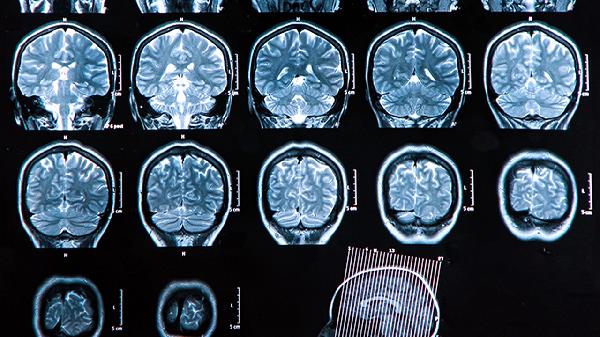

脑血栓片可用于缺血性脑血管病的治疗。缺血性脑血管病是由于脑部血液供应不足导致的疾病,常见症状包括头晕、头痛、肢体无力等。脑血栓片具有活血化瘀、通络止痛的作用,有助于改善脑部血液循环。遵医嘱使用脑血栓片时,需注意观察病情变化,避免自行调整用药方案。

脑血栓片适用于脑血栓形成的治疗。脑血栓形成是指脑血管内形成血栓,导致脑组织缺血缺氧。患者可能出现言语不清、偏瘫等症状。脑血栓片中的成分能够抑制血小板聚集,减少血栓形成风险。使用期间应定期复查,配合医生调整治疗方案。

脑血栓片可用于脑栓塞的辅助治疗。脑栓塞是由心脏或其他部位脱落的栓子阻塞脑血管所致,临床表现与脑血栓形成相似。该药物能改善微循环,减轻神经功能缺损。需严格遵医嘱用药,同时控制高血压、糖尿病等基础疾病。

脑血栓片对脑动脉硬化有一定治疗作用。脑动脉硬化是脑血管壁增厚、弹性减退的病理改变,可引发慢性脑供血不足。该药物能扩张脑血管,增加血流量。使用时需结合生活方式干预,如低盐低脂饮食、适度运动等。

脑血栓片可用于中风后遗症的康复治疗。中风后患者常遗留肢体功能障碍、语言障碍等症状。该药物通过改善脑部血液循环,促进神经功能恢复。康复期用药需长期坚持,配合针灸、康复训练等综合治疗。